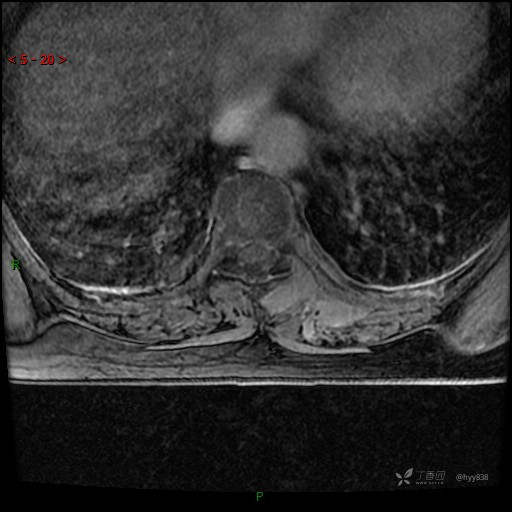

MRI AXI T2WI